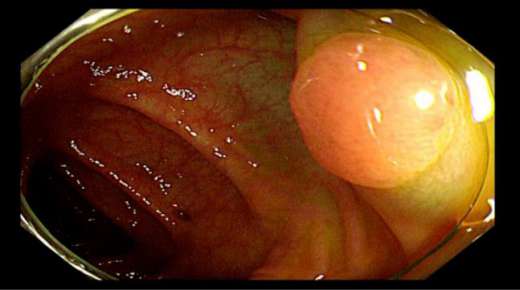

距肛門16cm直腸白光下較大息肉在檢查過(guò)程中我們發(fā)現,C先生在升結腸回盲瓣附近、橫結腸、直腸等部位多發(fā)息肉,個别息肉較大,甚至達到1.5cm以上。且通過(guò)NBI技術進(jìn)行觀察,息肉已經(jīng)有了病變的不良趨勢。

我們在腸鏡檢查過(guò)程中爲C先生切除了息肉,幸虧發(fā)現和處理及時,才避免了息肉的進(jìn)一步病變。如果再晚一些進(jìn)行檢查,這(zhè)些息肉有很大可能(néng)發(fā)展爲早癌。雖然C先生日常沒(méi)有症狀,也沒(méi)有家族史,但這(zhè)些并不是排除風險的可靠依據。隻有胃腸鏡檢查才是發(fā)現消化道(dào)早癌的金标準,盡早發(fā)現,盡早切除,才能(néng)最大限度避免息肉癌變。